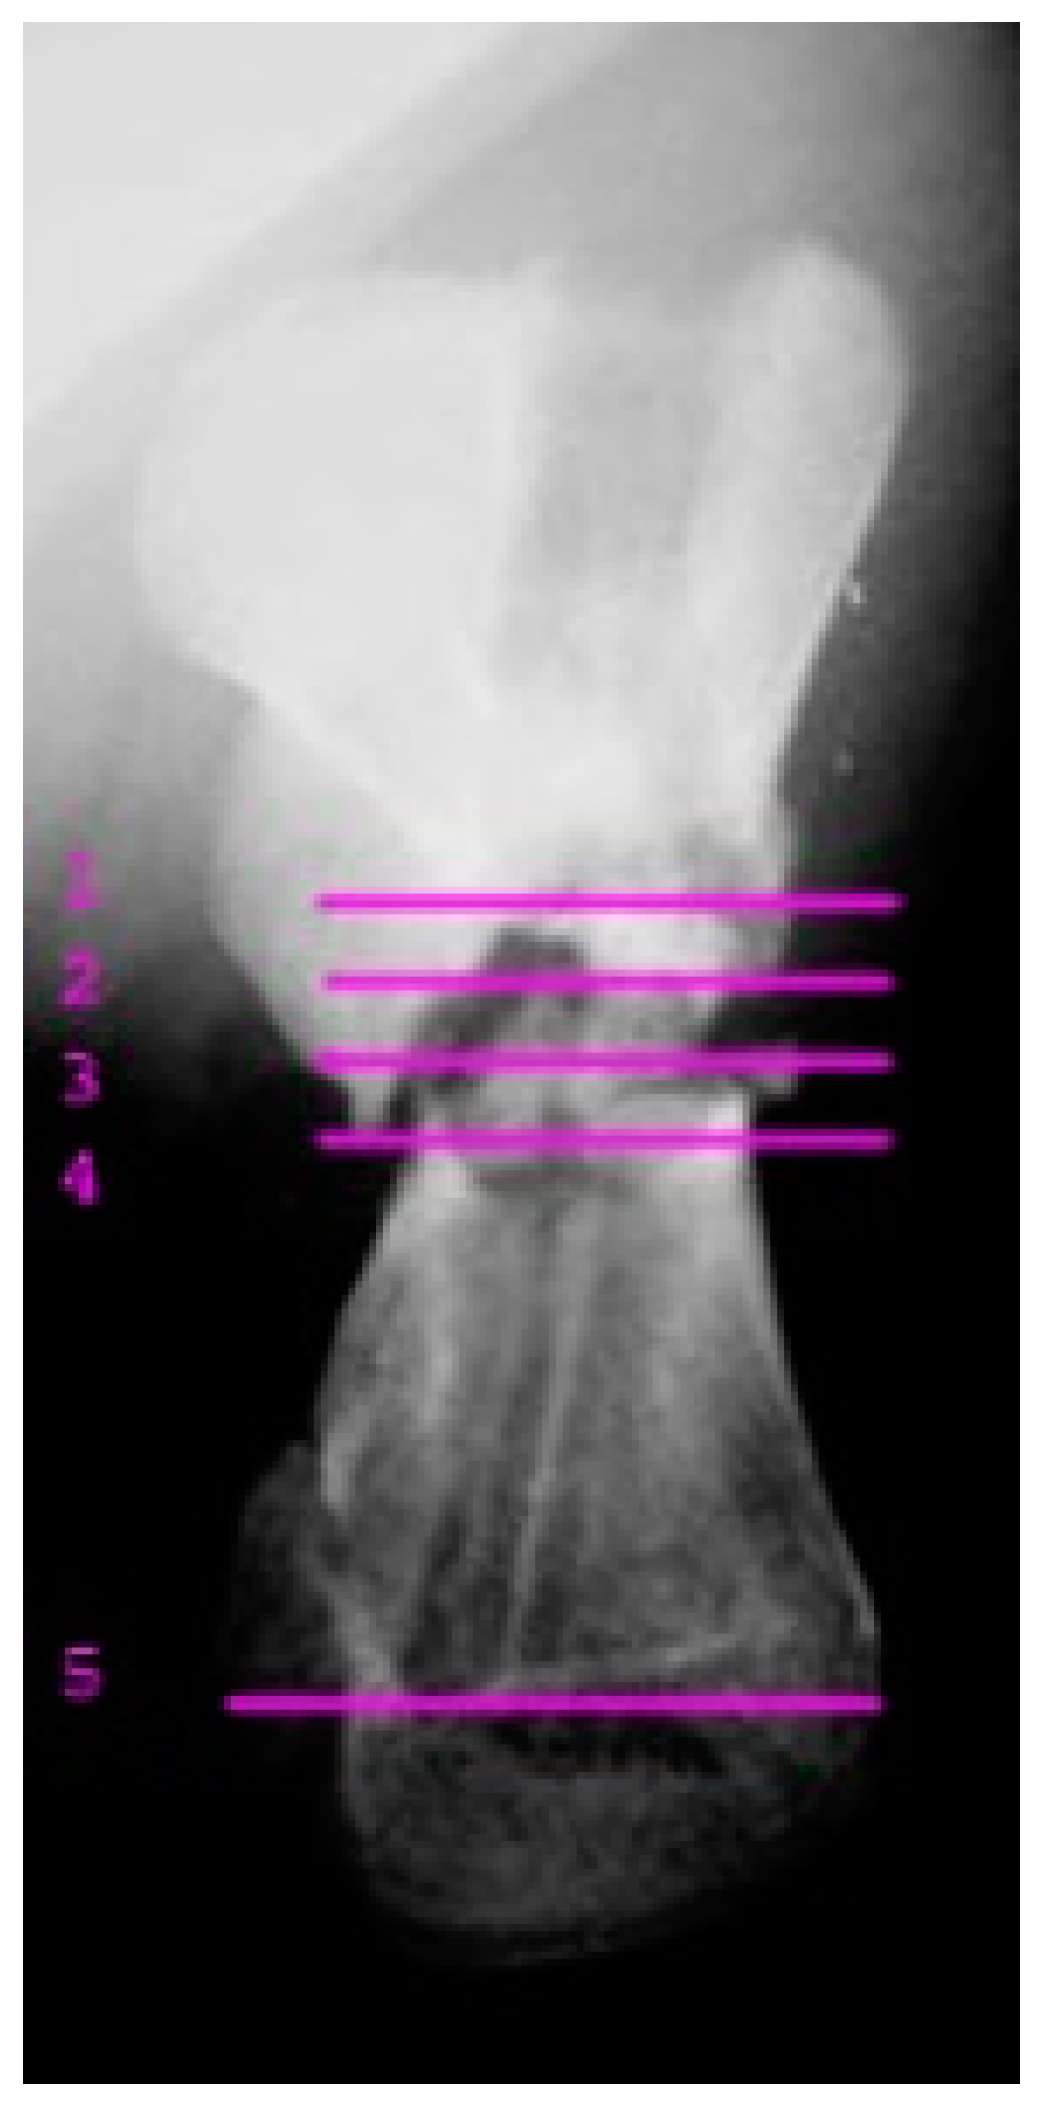

A juvenile sea turtle was presented to the Sea Turtle Clinic (STC) of Veterinary Medicine Department of the University of Bari with an entanglement lesion affecting the right front flipper. On admission, the sea turtle was measured and underwent a complete physical examination; curved carapace length (CCL) from notch to tip ranged 41 cm, curved carapace width (CCW) was 37 cm, and the weight was 18 Kg. The turtle appeared responsive but weak and dehydrated. Clinical evaluation of the musculoskeletal system performed out of the water showed swelling of the right front flipper and evidence of pain on deep palpation of the respective brachial muscle. A reduction in the right front flipper’s range of motion was observed when the turtle was examined in the water. Radiographic assessment, in dorso-ventral (D-V) and Caudo-Cranial (C-C) projections, indicated detachment of the distal epiphysis of the humerus, compatible with a type II Salter-Harris fracture, together with a transverse diaphyseal fracture (Figure 1). The turtle underwent general anesthesia, and the craniodorsal access to the humeral diaphysis was performed. The epiphyseal fracture was reduced by closed surgery and fixed using two crossed 2.5 mm Kirschner pins, introduced backward from the distal stump and brought out through the hyperflexed humerus-radio-ulnar joint. The same pins used to fix the epiphyseal fracture were inserted into the proximal stump to fix the diaphyseal fracture. After checking the stability of the fractures reductions, the surgically sectioned soft tissues were reconstructed, and post-operative radiographs were performed. Follow-up was performed after the surgery at 2, 4, 12, 16, and 24 months, when the turtle was released at sea. Three months after its release at sea, the turtle was caught dead in a fishing net at a depth of 40 m. To determine the evolution of bone repair from turtle release to death, the right humerus was removed for histological and histomorphometry analyses. Immediately after explant, the humerus was fixed in 4% buffered paraformaldehyde, dehydrated in ethanol, and embedded in methylmetacrylate. Serial cross sections, 750 µm thick, were cut at both the diaphyseal and epiphyseal fracture gaps using a circular diamond-bladed saw (Gillings Hamco) and were ground to a thickness of 100 µm. Sections were placed on a specimen holder and microradiographed using a microradiograph (Constant 1-K, Ital Structures, Italy) at a prefixed distance from the X- ray generator of 9.5 cm. X-ray exposure was set up at 8 kV and 14 mA. Contact microradiographs were obtained on Kodak high-resolution film (SO 343, Eastman Kodak Co., Rochester, NY, USA), developed with Kodak HC-110, fixed in Kodak UNIFIX, washed in distilled water and then airdried at room temperature. Sections were subsequently stained with 1% toluidine blue (pH 3.7) for mineralized tissue. Four separate levels were selected, three belonging to the mid-diaphyseal fracture gap, and one level to the epiphyseal fracture gap: the first and the fourth levels corresponded to the proximal and distal part of the callus, respectively, and the second and third levels to the center of the fracture (Figure 2). As a control, the left humerus, which had never been fractured, was processed with the same procedure. On the stained sections, using a Nikon DS-5 camera connected to a stereomicroscope (SMZ800, Nikon Europe B.V., Amstelveen, The Netherlands) and a DS camera control unit, the callus extension was measured and the amount of new laid down bone, cartilage, and fibrous tissue, expressed as percentage ratio of the entire section, were evaluated. Histomorphometry was performed using Nis-Elements BR analysis software (Nikon Europe B.V.).

Figure 1. Caudocranial radiograph of the anterior right flipper showing transverse diaphyseal and the type II Salter-Harris fractures.